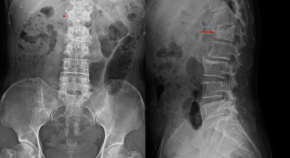

(A) The prevalence of PA was 6.1% of the total population. Among 55 patients with conclusive subtype differentiation of PA, 27% had APA, 65% had BAH, and 7% had UAH. (B) Patients with PA had a higher blood pressure and higher prevalence of target-organ damage than patients without PA. APA, aldosterone-producing adenoma; BAH, bilateral adrenal hyperplasia; ECG, electrocardiogram; LVH, left ventricular hypertrophy; PA, primary aldosteronism; SBP, systolic blood pressure; UAH, unilateral adrenal hyperplasia.